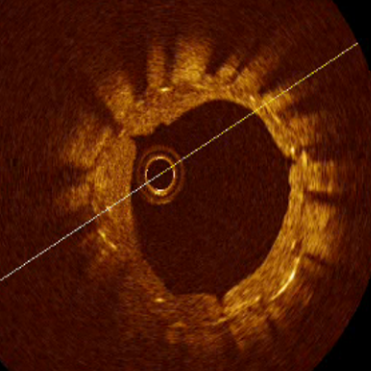

普通球囊与特殊球囊扩张狭窄血管腔比较

普通球囊扩张

鼎科定向刻痕球囊扩张